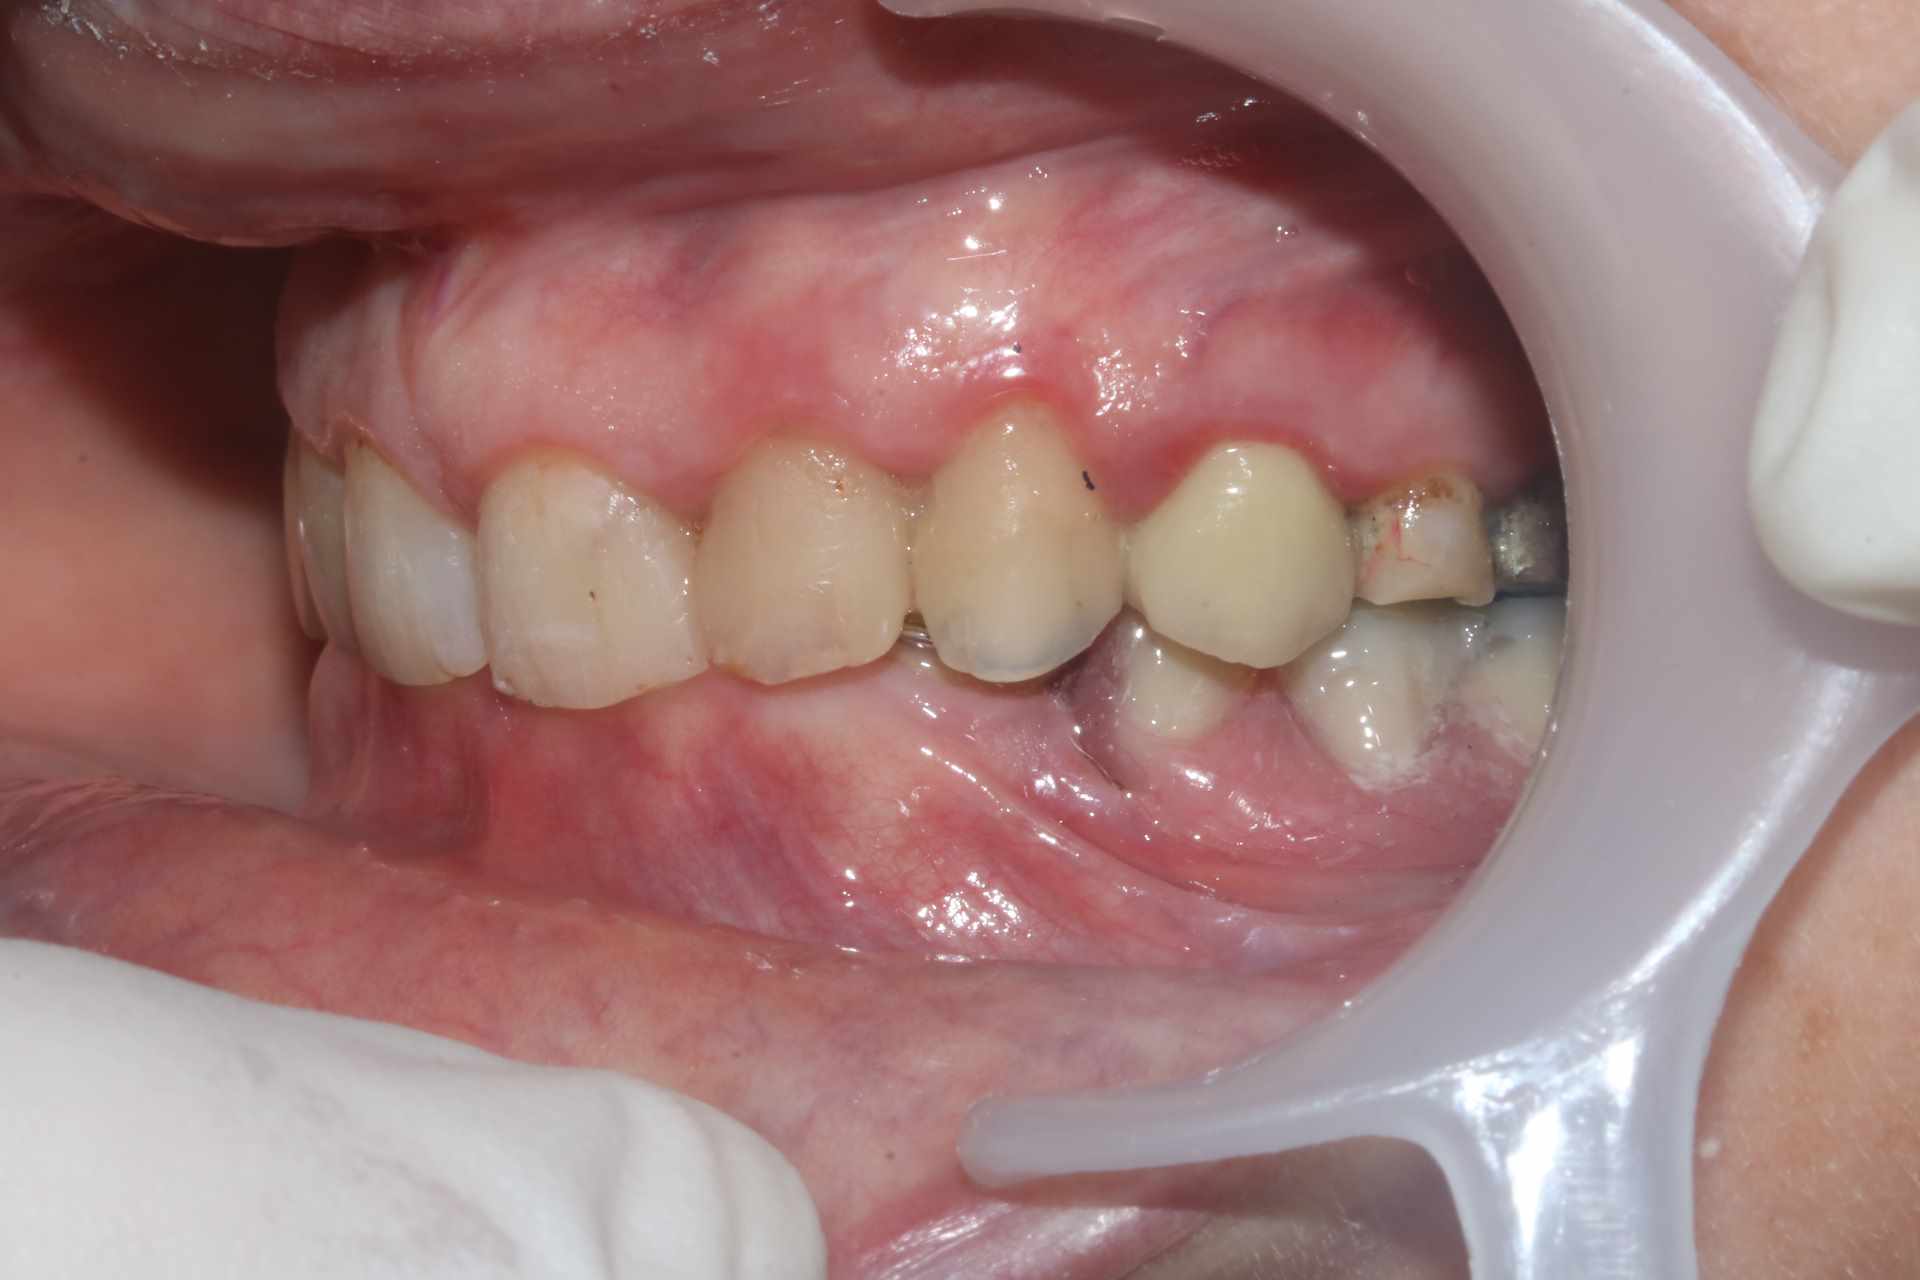

La patiente venait pour 34 35 descellées et 13 mobile. J'en suis encore au stade on traite les urgences avant de s'attaquer vraiment au cas. Vous voulez pas me donner un coup de main ? je ne sais pas trop par ou commencer !

On a une classe 2 2 majeure. ultra verrouillée. Je ne vois pas comment m'en sortir sans augmenter la DV qui a été malmenée par les soins et couronnes diverses a peu près tous en sous occ à mon avis sauf la 13 qui a explosé.

Je dis ça parce qu’ on constate quand même peu d’usure sur les dents encore saines et elle a une fameuse supra-alvéolie maxillaire.

Son pb est un pb de décentrage sur la gauche du à tous les coups au départ par la canine trop épaisse en cingulum .

et les autres couronnes ont pérennisé le bordel .

Oui la couronne sur sur 13 c'est une honte, volumineuse et beaucoup trop longue. Je suspecte une couronne faite avec un mordu unilatéral pour expliquer une telle aberration.

Sur 34 35 il y avait des couronnes jumelées qui se sont descellées peu après que la 13 se descellée / fracture.